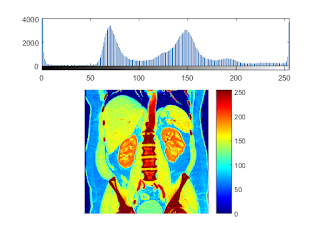

perform the color map of a CT image

colormap(jet); caxis caxis([0,255]);

ans =

0 255